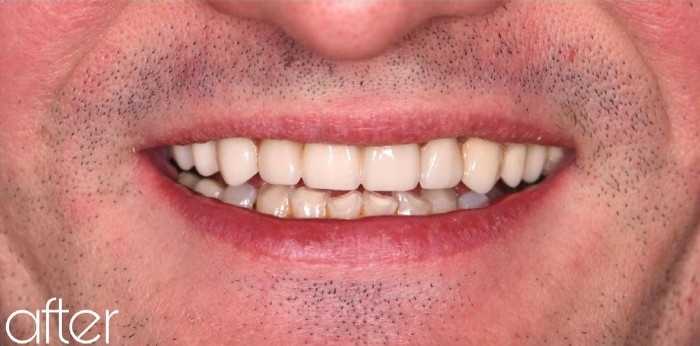

Установка керамической коронки

Результат, как говорится «на лицо» и тот случай, когда «реальность» превзошла «ожидание»!

Что сделано?

Протезирование 3х центральных единиц безметалловыми коронками из прессованной керамики (на фото «до» была реставрация, срок службы которой истёк, коронки будут радовать в несколько раз дольше)

Чья работа?

Иван Сергеевич Зулинский

Доктор: Зулинский Иван Сергеевич